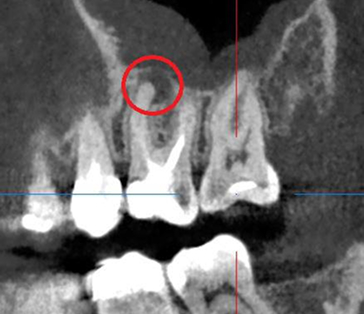

Сохранение зуба при наличии кисты, проростающей в гайморову пазуху

Проблема: У пациента боли в проекции гайморовой пазухи, заложенность носа, боли при пережевывании пищи.

Лечение: Проведено эндодонтическое перелечивание зуба под микроскопом: удалены ранее внесённые материалы, выполнена тщательная механическая и медикаментозная обработка корневых каналов с учётом их анатомии. Особое внимание уделено устранению инфекционного очага (кисты), связанного с воспалением в области гайморовой пазухи. После этого каналы герметично запломбированы, а коронковая часть зуба временно восстановлена для дальнейшего покрытия зуба коронкой.

Результат: После проведённого эндодонтического лечения болевые ощущения при жевании устранены, дискомфорт и давление в области гайморовой пазухи исчезли, восстановилось нормальное носовое дыхание. Зуб сохранён, его функция восстановлена. После фиксации коронки полностью восстановлены анатомическая форма и жевательная эффективность, нагрузка распределяется корректно.